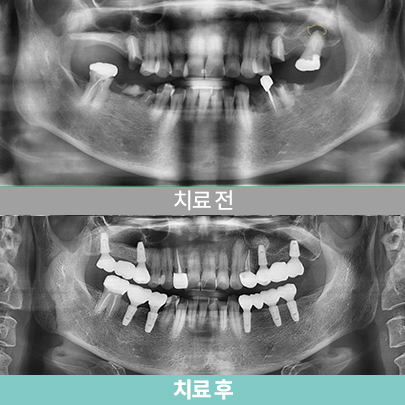

- 송곳니 발거+골이식+임플란트식립, 치료 후 5개월

- 심미보철

- 심미보철

- 골소실 부위 임플란트

- 송곳니 발거+골이식+임플란트식립, 치료 후 5개월

- 심미보철

- 심미보철

- 골소실 부위 임플란트